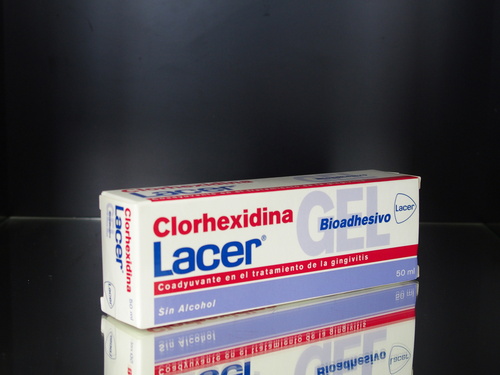

吉本歯科医院ではインプラント患者さんのために薬監証明による輸入許可を取って輸入している。スペイン製の薬用歯磨き粉やイタリア製ヒアルロン酸洗口液があります。

やむなく効果の高いホワイトニング剤や薬用歯磨き粉やヒアルロン酸洗口液は輸入しているのです。

そしてさらには

「ヒアルロン酸のうがい薬」

「クロロヘキシジンの殺菌剤」の歯磨き粉もおすすめです。

吉本歯科医院ではインプラント患者さんのために薬監証明による輸入許可を取って輸入している。スペイン製の薬用歯磨き粉やイタリア製ヒアルロン酸洗口液があります。

やむなく効果の高いホワイトニング剤や薬用歯磨き粉やヒアルロン酸洗口液は輸入しているのです。

そしてさらには

「ヒアルロン酸のうがい薬」

「クロロヘキシジンの殺菌剤」の歯磨き粉もおすすめです。